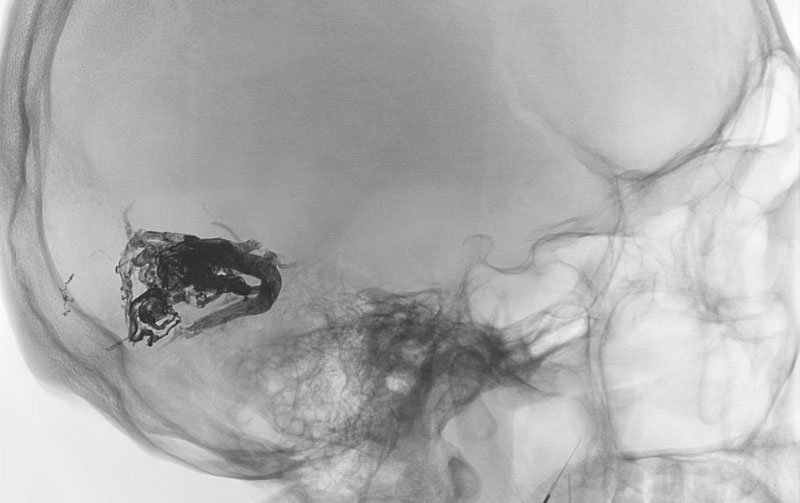

No.1596 手術前

No.1596 手術中

No.1596 手術後

くも膜下出血

左中大脳動脈瘤破裂

40代

救急外来